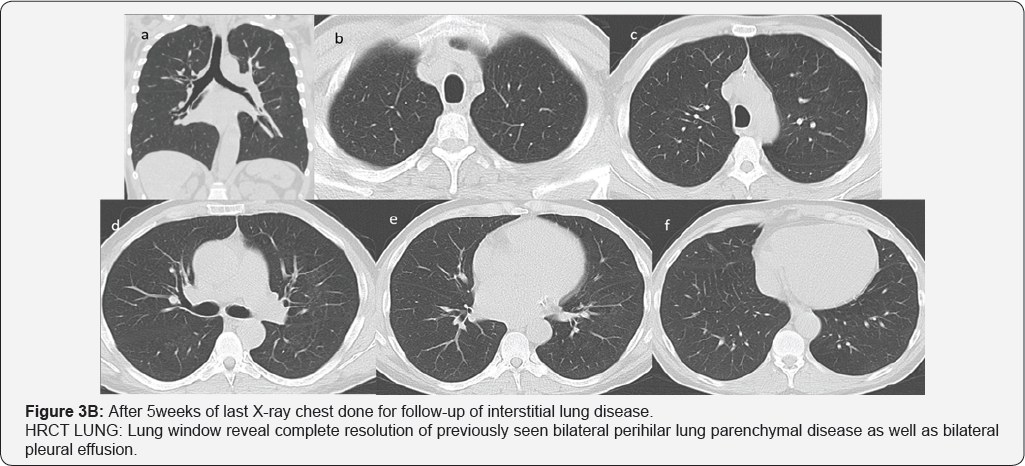

Pleural effusion (RT>LT) multiple small mediastinal lymph nodes (arrow in image a & b), likely reactive. Bilateral perihilar airspace diffuse air space opacity and ground-glass attenuation with superimposed interlobular septal thickening and intralobular lines (LT> RT). Common differential of Crazy paving given as well as diagnosis of pulmonary edema (uncommon cause of crazy paving) given in view of history of CHF and improvement by treatment. Superimposed infection is likely in view of high inflammatory markers (Figures 3A & 3B).